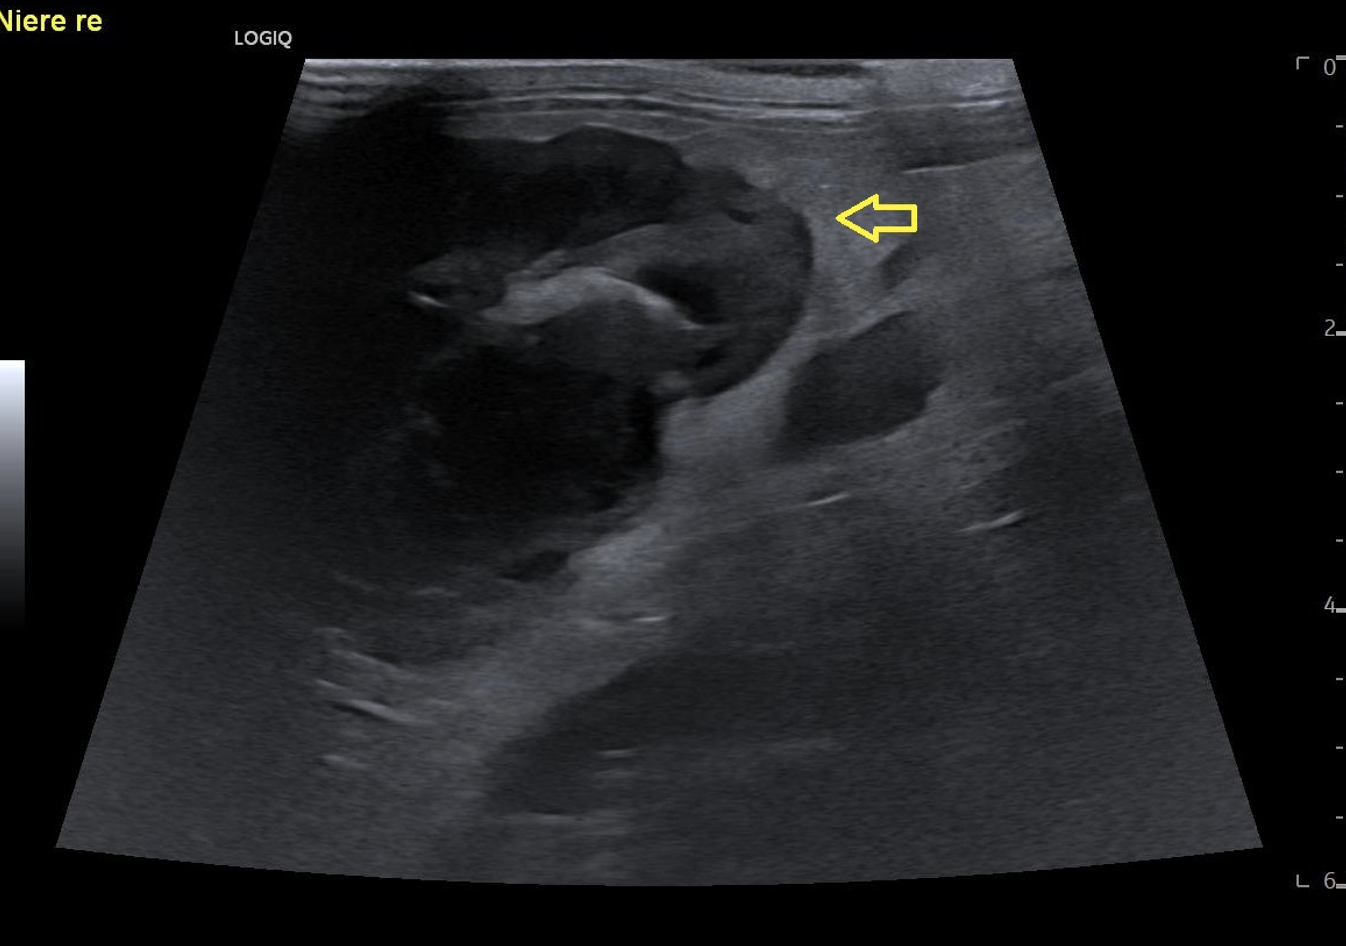

Die Röntgenuntersuchung zeigte eine weichteildichte Masse im rechten mittleren Abdomen sowie eine radiodichte Struktur dorsal der Harnblase. Die Sonographie ergab eine deutlich veränderte rechte Niere mit hochgradiger Hydronephrose sowie eine ausgeprägte Peritonealreaktion. Der rechte Ureter war stark dilatiert mit einer schallschattenbildenden Struktur kurz vor der Einmündung in die Harnblase. Die linke Niere sowie der linke Ureter waren sonographisch unauffällig. Auf Basis dieser Befunde wurde die Diagnose einer hochgradigen rechtsseitigen Hydronephrose sekundär zu einer Ureterolithiasis gestellt.